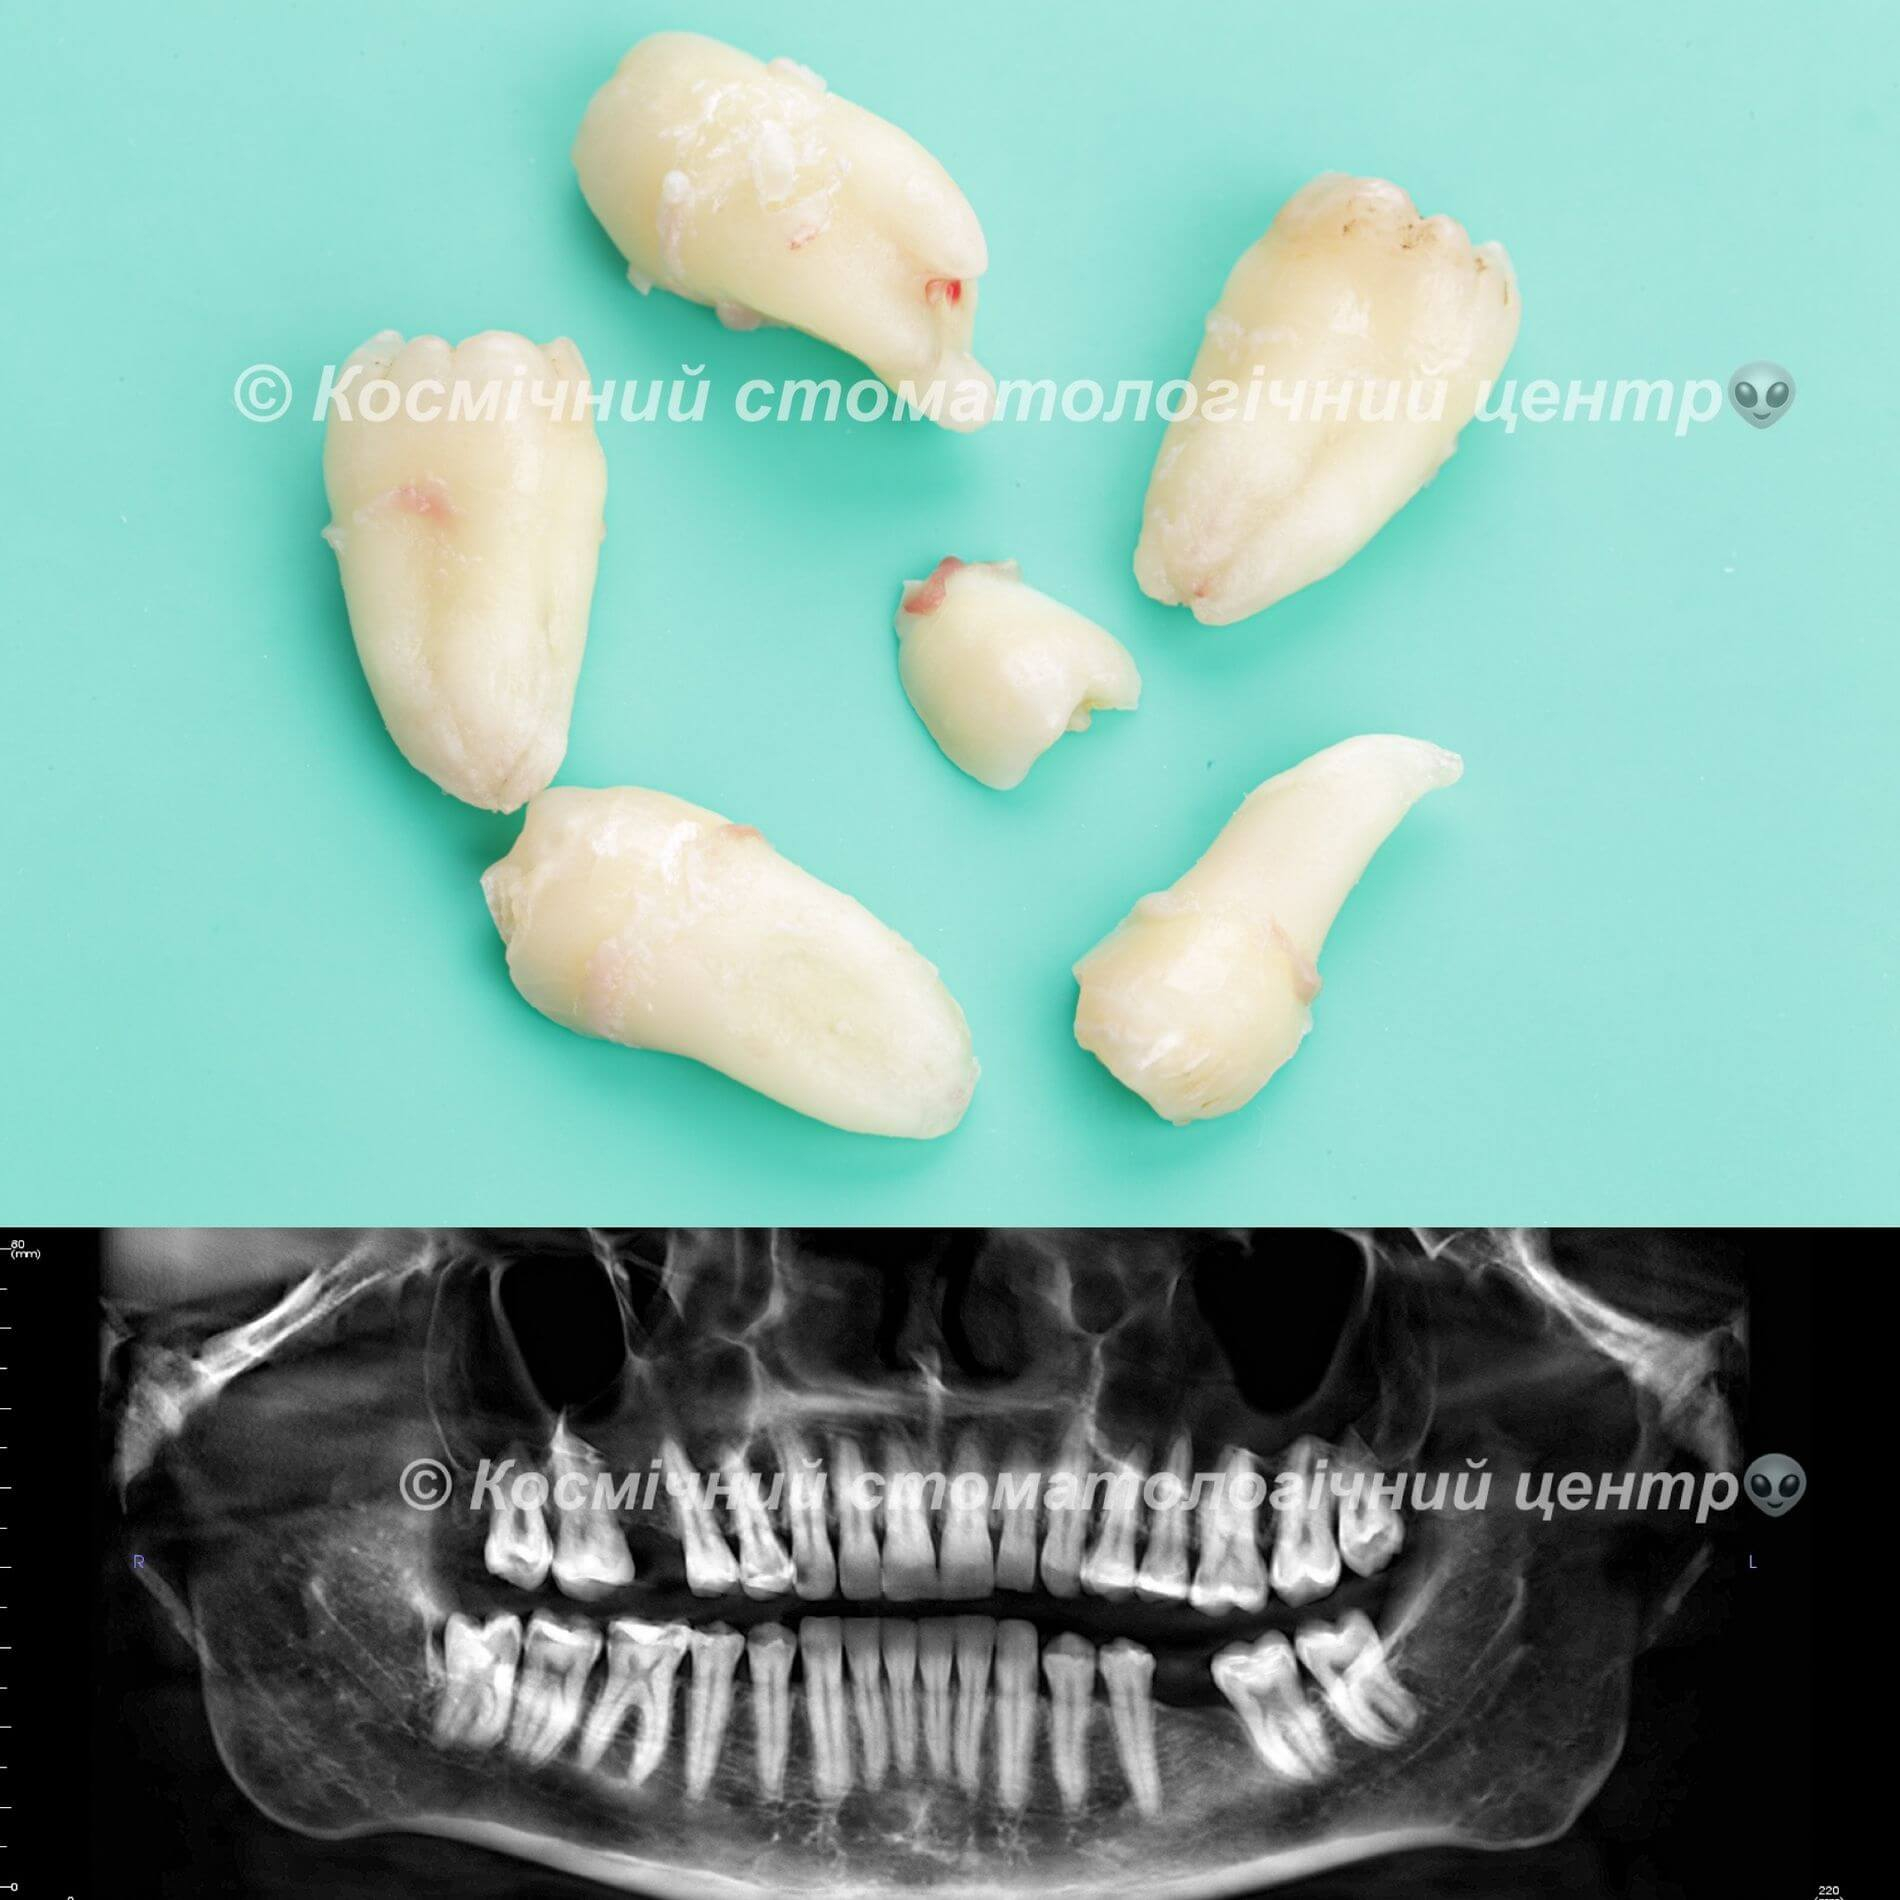

• Полное удаление зуба - если зуб полностью прорезался и имеет сросшиеся корни.

• Отдельное удаление коронки зуба и его корней - если зуб прорезан и корни растут по отдельности.

• Удаление зуба по схеме 1 или 2 с разрезом десен - если зуб прорезан частично.

• Разрез десен, освобождение зуба от близлежащей кости ультразвуком и удаление по схеме 1 или 2 - если зуб не прорезался, но беспокоит.

Вырвать зуб мудрости во Львове можно проще, чем тебе кажется, в Космической стоматологии Драганчука. Начни этот путь с простого шага - первичной встречи с хирургом-стоматологом. На консультации мы сделаем основное - направим тебя на 3D компьютерную томографию, чтобы учесть близость нижнечелюстного нерва (нижние 8-ки) и верхнечелюстной пазухи (верхние 8-ки) и составим план удаления зубов.

Вырвать зуб мудрости во Львове можно проще, чем тебе кажется, в космической стоматологии Драганчука. Начни этот путь с простого шага – первичной встречи с хирургом-стоматологом. На консультации мы сделаем основное – направляем тебя на 3D компьютерную томографию, чтобы учесть близость нижнечелюстного нерва (нижние 8-ки) и верхнечелюстной пазухи (верхние 8-ки) и составим план удаления зубов.